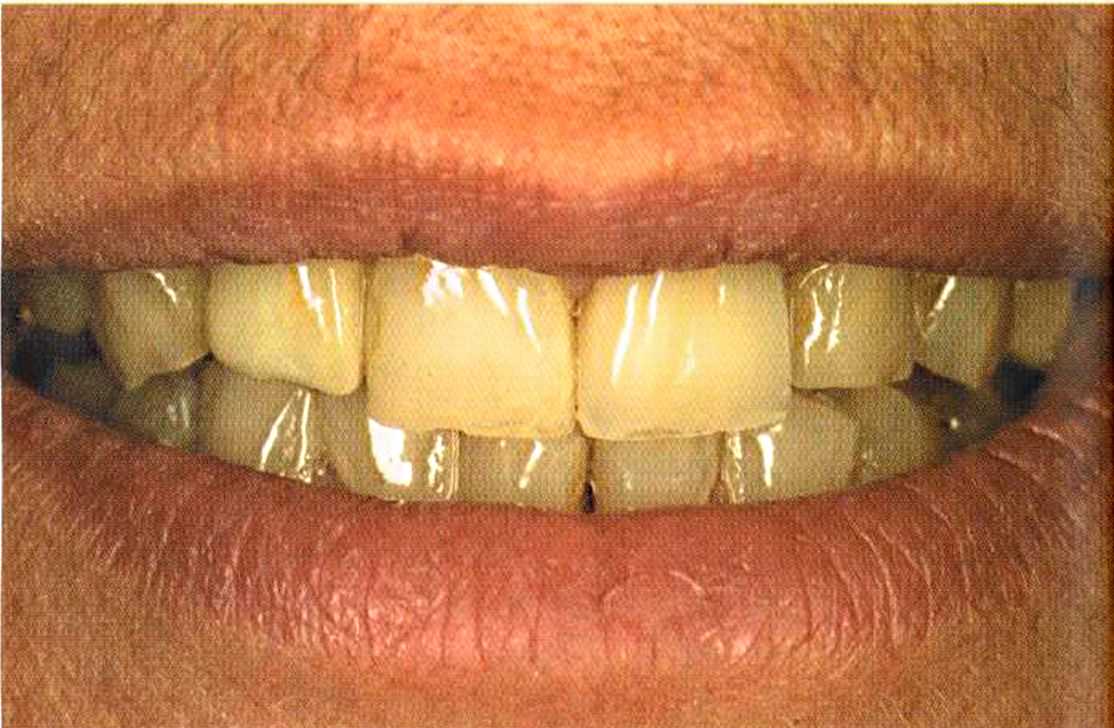

Зафиксированные на цемент коронки в полости рта. Видны излишки цемента, которые потом легко удалить, они отскакивают, как яичная скорлупа.

Только что зацементированные коронки. До сих пор сохранилось воспаление десневого сосочка. Уже через несколько дней он будет здоровым, бледно-розового цвета.